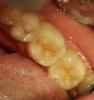

METT Опубликовано 22 марта, 2013 Автор Поделиться Опубликовано 22 марта, 2013 НОвенькое Ссылка на комментарий

METT Опубликовано 22 марта, 2013 Автор Поделиться Опубликовано 22 марта, 2013 И еще Ссылка на комментарий